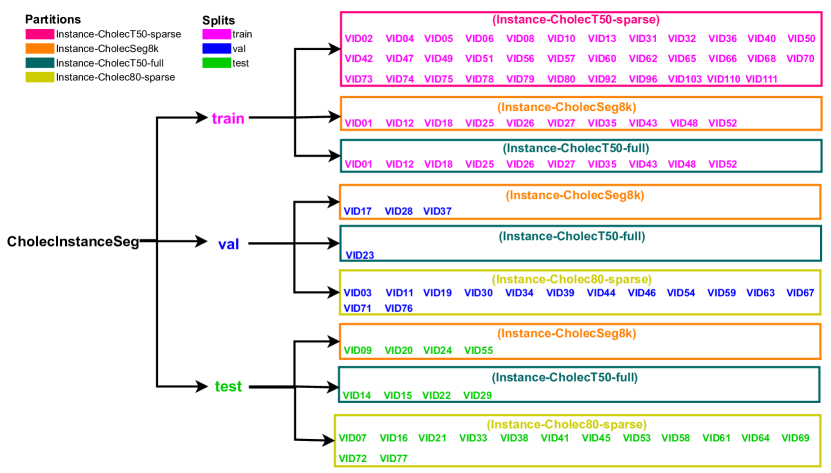

Recommended Data Splits

To facilitate effective training, validation, and testing of neural networks for instance segmentation, we divide CholecInstanceSeg into standard training, validation, and testing subsets. This division considers the partitions and shared sequences within the dataset.

For the training dataset, we included the entire Instance-CholecT50-sparse partition, which consists of 35 sequences with 2,681 frames. This partition offers significant diversity in surgical scenes due to its varied sequence content. Additionally, 10 in Instance-CholecSeg8k and the 10 sequences in Instance-CholecT50 which come from the same video (shared) were included in the training dataset to avoid redundancy in the validation and testing subsets.

The validation dataset contains 3 out of 7 sequences which are unique to Instance-CholecSeg8k. Similarly, from Instance-CholecT50-full, 1 out of 5 sequences which are unique to Instance-CholecT50 were included in the validation dataset. Additionally, half of the sequences from Instance-Cholec80-sparse were added to the validation dataset to bolster its diversity.

The test dataset includes the remaining 4 unshared sequences from Instance-CholecSeg8k and the remaining 4 unshared sequences from Instance-CholecT50-full. The other half of the sequences from Instance-Cholec80-sparse were also included in the test dataset. This division ensures that the test set includes a wide range of scenarios (sequences), providing a comprehensive assessment of model performance.

The final split for the dataset is as follows: the training set contains 55 sequences (26,830 frames), the testing set includes 23 sequences (11,299 frames), and the validation set comprises 17 sequences (3,804 frames).

A visual representation of the recommended dataset split can be seen in Figure 9. We provide scripts to convert the downloaded zip file into a train, test, and validation format based on these recommended splits.